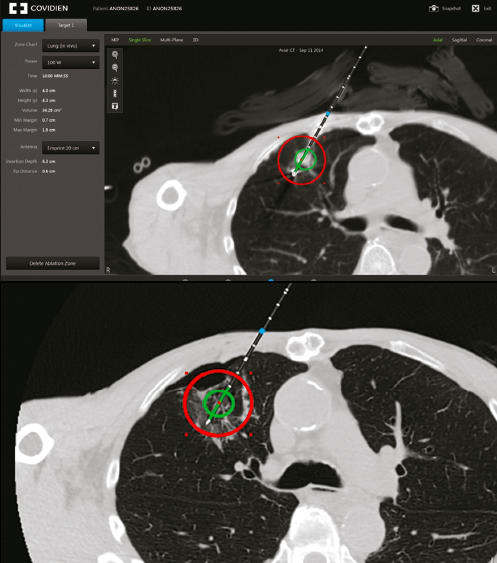

Medtronic’s latest innovation, the Emprint™ ablation system with Thermosphere™ technology, offers more predictable and repeatable results than other techniques and devices (See Figure 1). These advantages come from the fact that Thermosphere™ technology enables precise control of an EM field independent of the surrounding tissue environment.

The Emprint™ ablation system with Thermosphere™ technology realizes the promise of predictability. It gives physicians the ability to easily control the thermal energy delivered by allowing precise control of the EM field across tissues and temperatures. This allows clinicians to accurately predict the boundaries and characteristics of the ablation zone.

Radiometers measure EM radiation and enable the characterization of the spatial distribution of an EM field. Ladtkow’s team is incorporating radiometers into Medtronic probes in order to give clinicians real-time feedback about the ablation zone. This will enable a clinician to fine-tune the zone as needed during the procedure, and to make sure the radiation destroys the targeted tissues while minimizing effects on the surrounding healthy tissue. (See Figure 2)